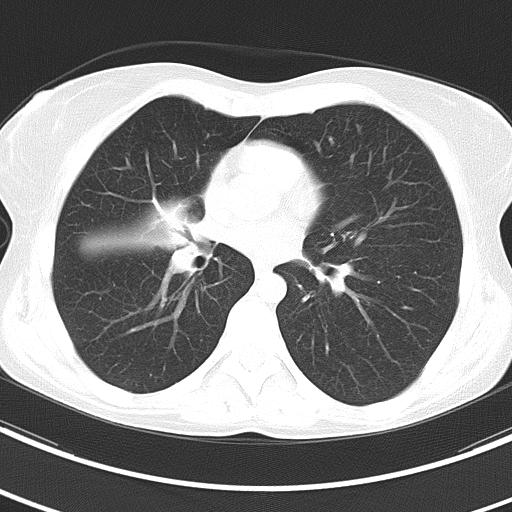

CT:  mucoid impactatio a középső lebeyhörgőben